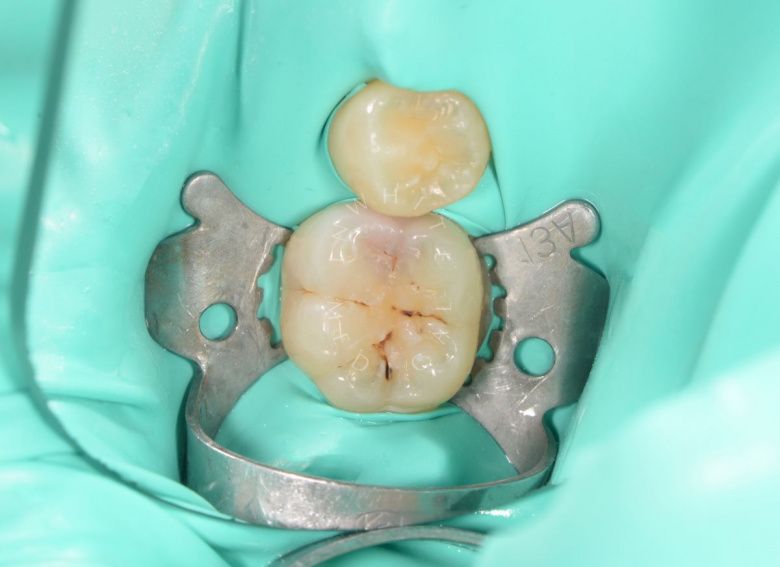

Лечение молочных зубов и установка металлических коронок во сне

Результат